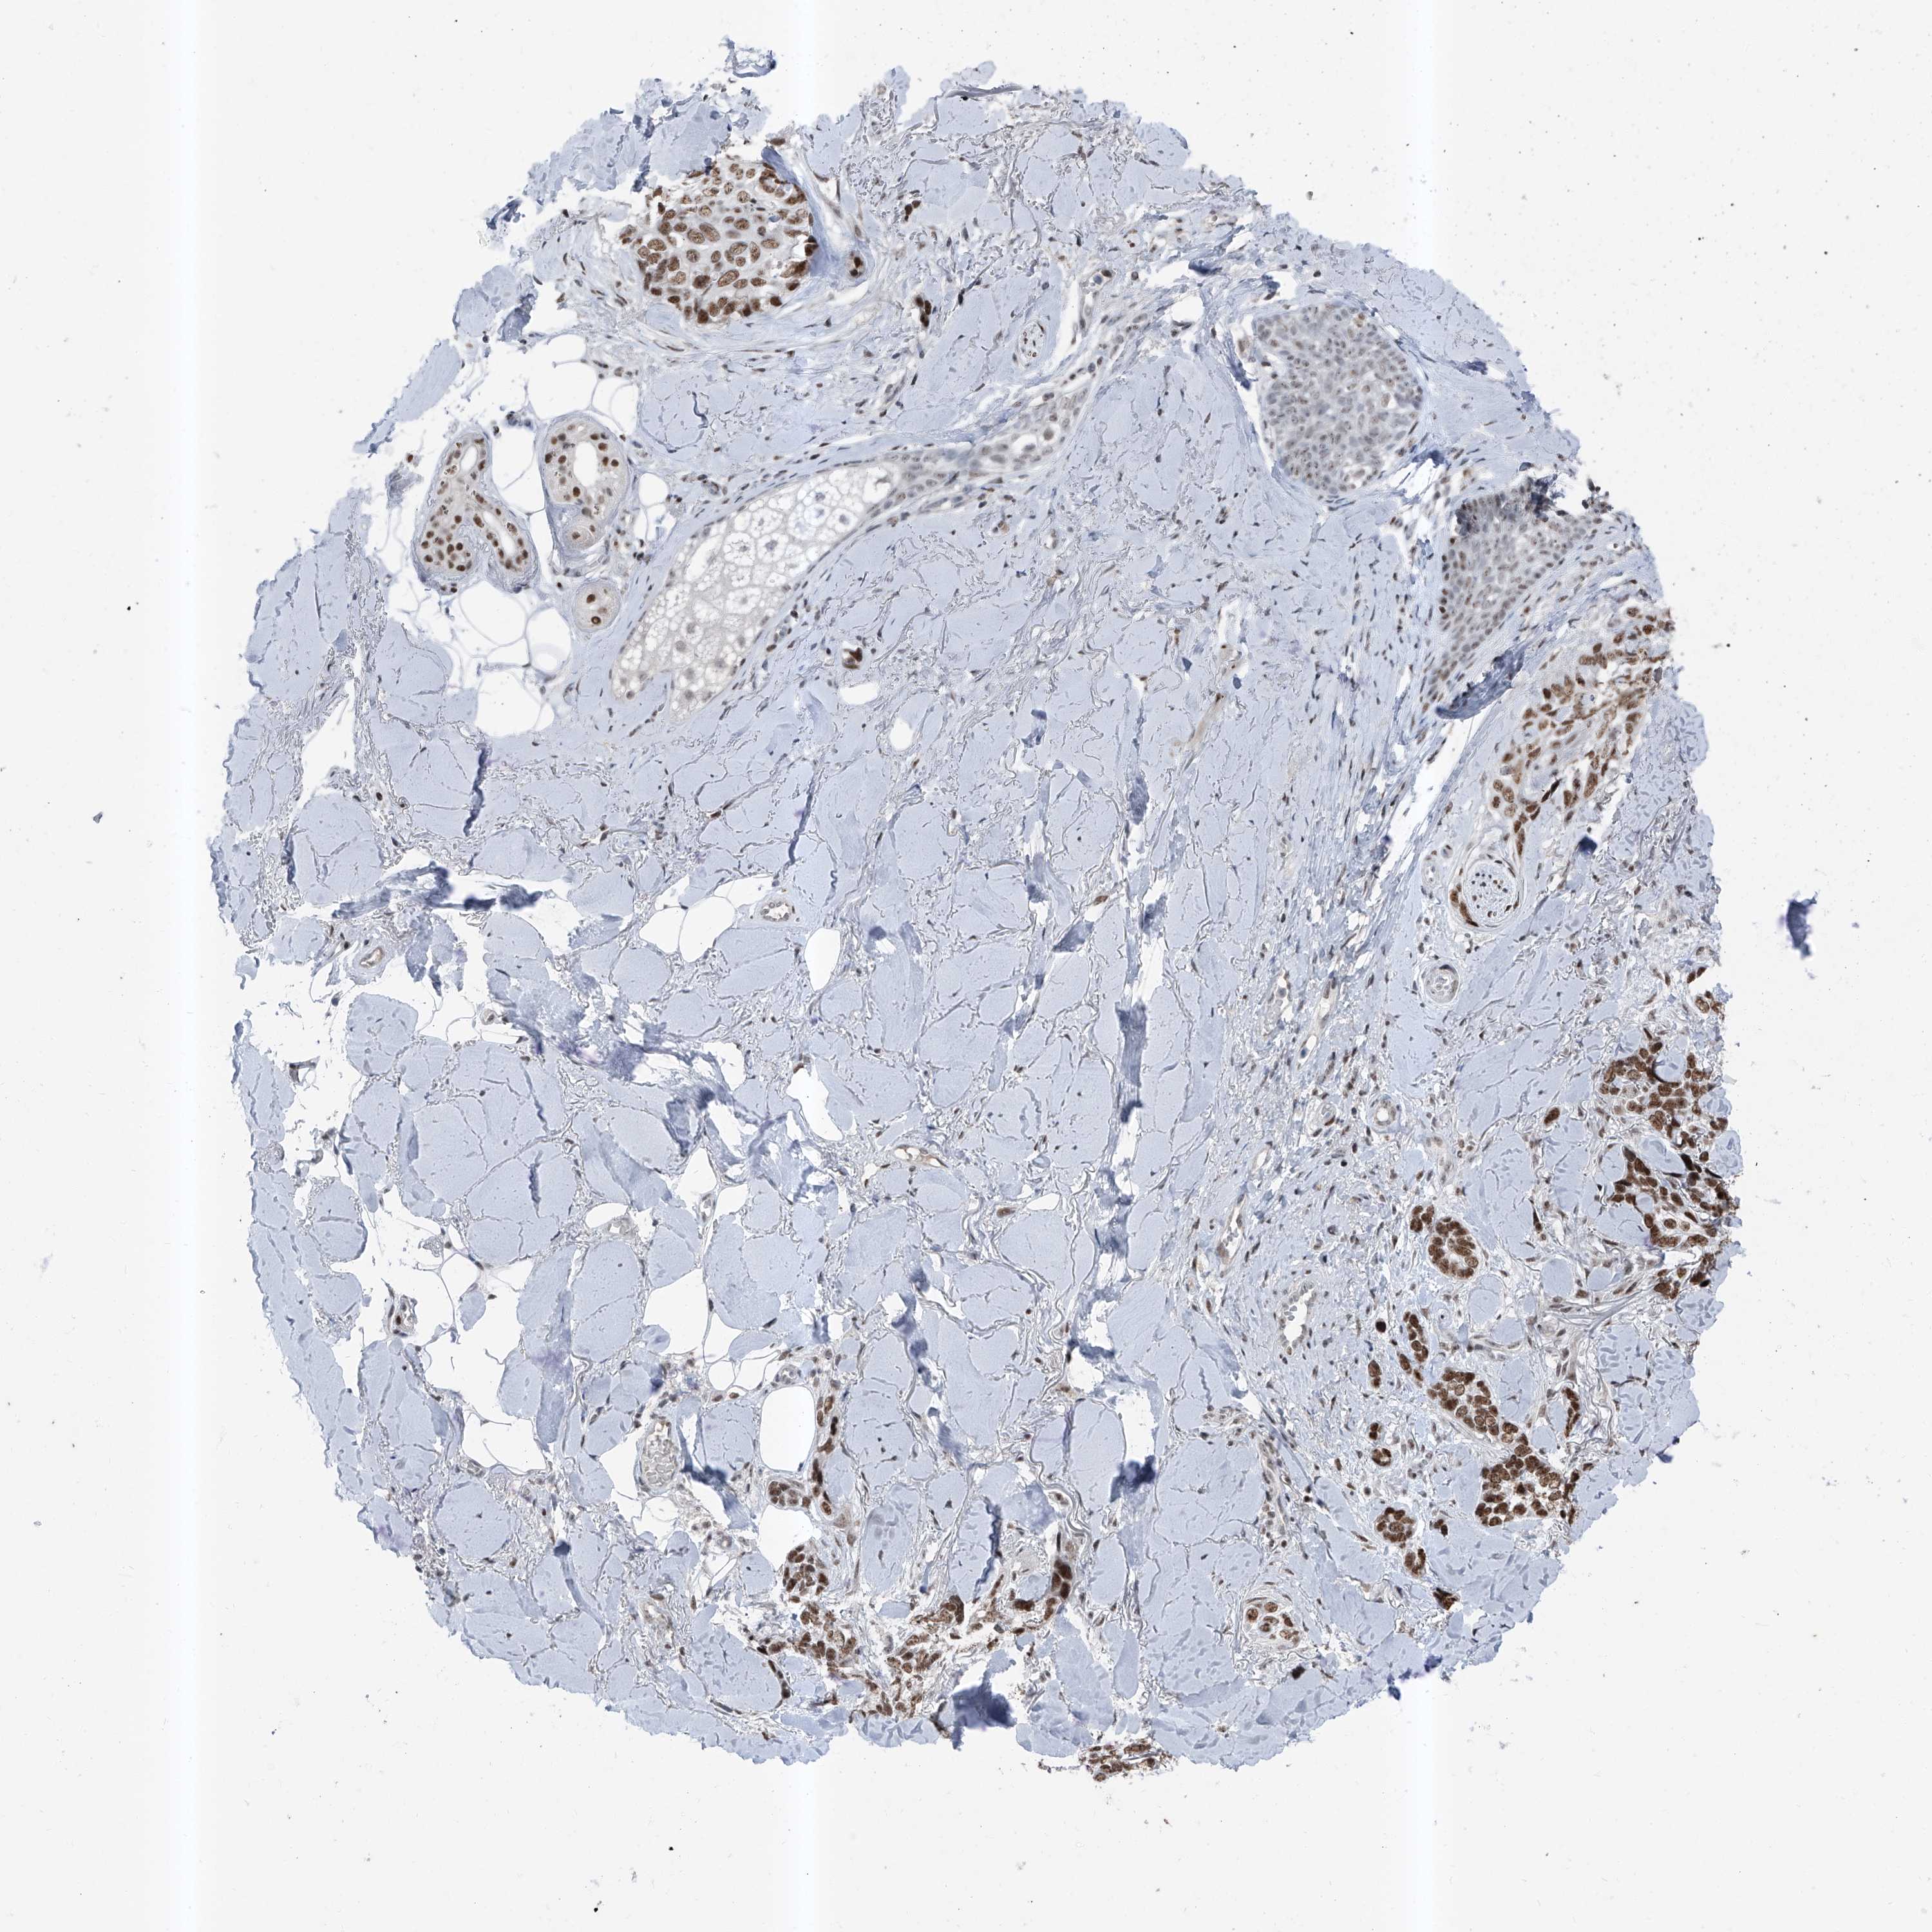

SKIN CANCER - Protein expressioni

A mouse-over function shows sample information and annotation data. Click on an image to view it in a full screen mode. Samples can be filtered based on level of antibody staining by selecting one or several of the following categories: high, medium, low and not detected. The assay and annotation is described here.

Antibody stainingi

Antibody staining in the annotated cell types in the current human tissue is reported as not detected, low, medium, or high, based on conventional immunohistochemistry profiling in selected tissues. This score is based on the combination of the staining intensity and fraction of stained cells.

Each image is clickable and will lead to virtual microscopy that enables deeper exploration of all samples and also displays staining intensity scores, fraction scores and subcellular localization as well as patient and tissue information for each sample.

Antibody HPA030472

Antibody HPA036584

Basal cell carcinoma